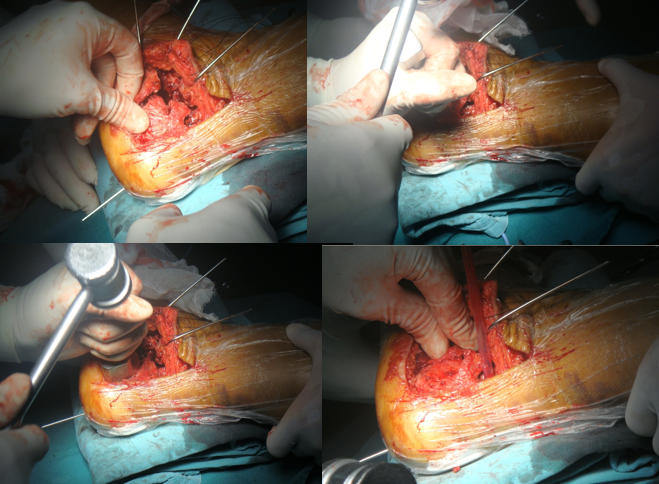

技巧三、克氏针的位置剥离骨膜后,3根克氏针牵开皮肤。注意距骨前后一根,骰骨一根。这样显露充分

骨刀将跟骨外侧壁翻开,同时跟骨内翻即可清晰显露距下关节和跟骨后关节面

技巧四、如何恢复跟骨的长度以及高度这样撬拨恐怕只能恢复跟骨的高度,因为没有纵向的牵引。

我们的方法是:大巾钳位于跟骨结节上方,向下后牵引跟腱

技巧五、如何恢复跟骨的后关节面

牵引下骨刀根据距骨关节面,撬起协助恢复后关节面形态

一旦后关节面位置恢复,用2mm克氏针将较大的骨块钉在距骨上。维持复位的状态。

按照上述的1、2、3步(一牵二撬三穿)操作,即可完成跟骨高度、长度、后关节面的恢复。

Bohler“s角、Gissan”s角如果透视可显示正常。

技巧六、如何恢复跟骨的宽度对于Sander‘s分型Ⅳ型骨折,外侧壁膨出,跟骨增粗明显。这时可以用简单的暴力给予复位-----锤击

它带来的额外收益是:跟骨体部的骨质缺损间隙消失,而不必植骨。

复位的工具

在放跟骨板之前,用击锤锤击跟骨外侧壁,恢复跟骨宽度。此时应保持克氏针在维持正常的复位位置

它带来的额外收益是,跟骨体部的骨质缺损间隙消失,而不必植骨。